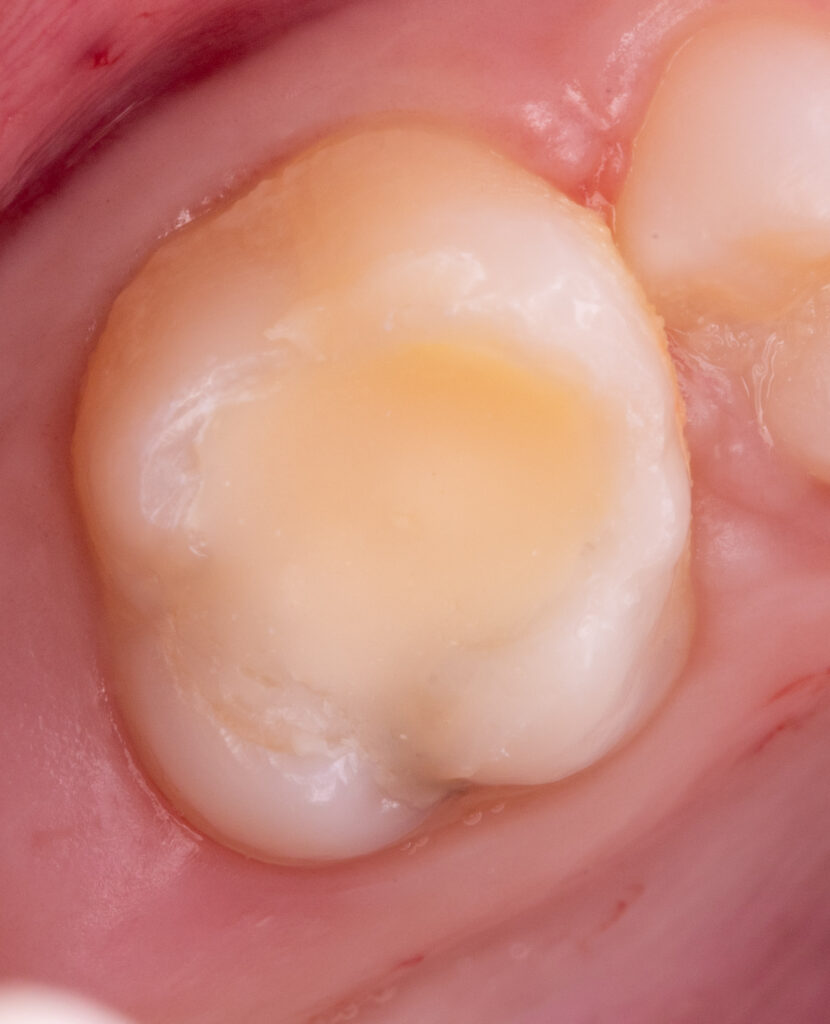

An 11-year-old girl presented with a history of root canal treatment on tooth 2.6 performed two years ago.

Radiographic examination revealed no signs of inflammatory processes in the root canal system. However, a flat and inadequate restoration was detected and required replacement.